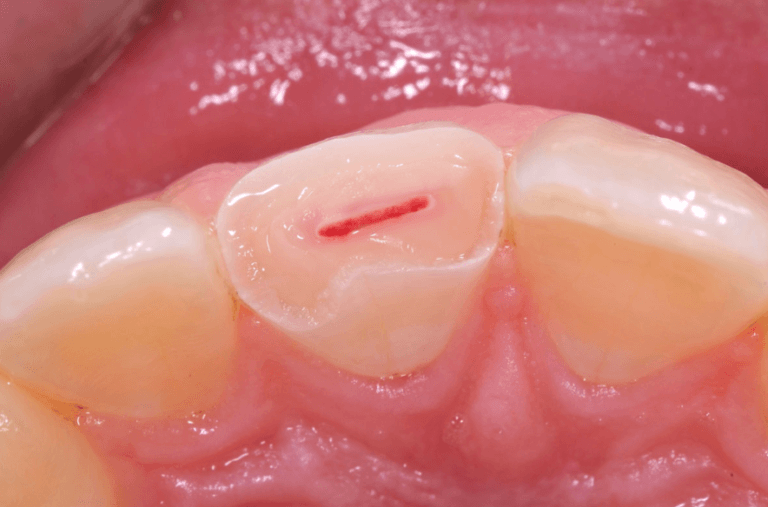

direct pulp capping procedure clinical photo

3. Coiffage Pulpaire Direct

Définition

Consiste à placer un matériau biocompatible au contact direct d’une petite parcelle de tissu pulpaire mis à nu, recouvert par un matériau d’obturation coronaire définitif (Willershausen et coll., 2011).

Indications Thérapeutiques

Catégories I ou II de Baume uniquement.

• Lésions carieuses : si possibilité de reconstituer la dent, pulpe vitale sans douleur spontanée, pose de la digue possible, restauration étanche garantie

• Traumatismes : exposition pulpaire peu étendue (< 1 mm), pulpe saine, traumatisme de moins de 24 heures, délabrement coronaire limité

• Expositions pulpaires iatrogènes : si conditions aseptiques maintenues, pulpe non inflammée ni infectée, exposition minime (< 0,5 mm)